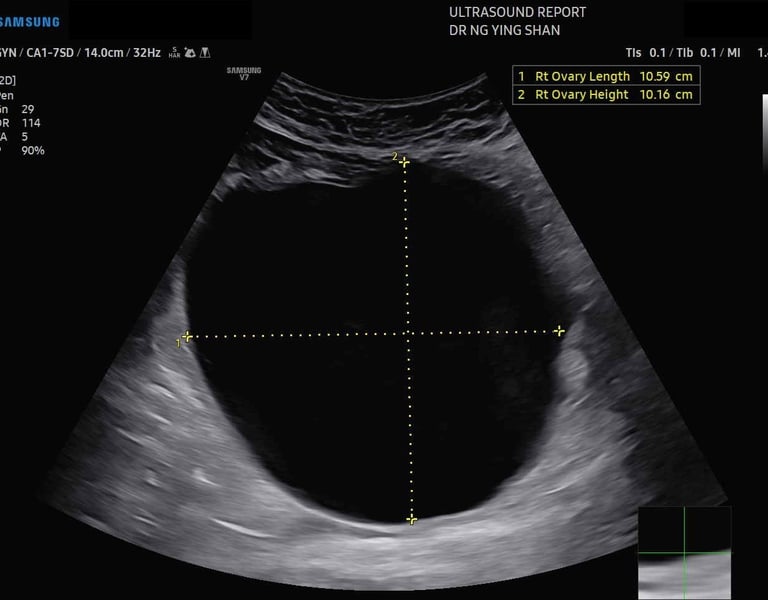

Ovarian cyst Kuching Gynae Kuching古晋妇产科 古晋卵巢

No, a blood test cannot directly detect a cyst. The most common and effective method for detecting ovarian cysts is an ultrasound scan.

Ultrasound scan